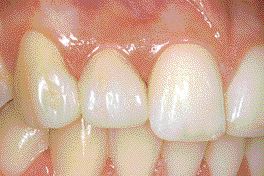

Combining Orthodontic and Restorative Treatment to Optimize Esthetics and Function In Space Management Cases

FIGURE 9

By Daniel Fortin, DMD, MS; Genevive Guertin, DMD, MS; Athena Papadakis BDS (Hons), FDS, RCS (Eng), M.Sc., FRCDC ABSTRACT Clinical management of patients with spacing of the anterior teeth following orthodontic treatment is often necessary. When creating space orthodontically, a number of important questions arise as restorative treatment will often require orthodontic space redistribution prior … Read more